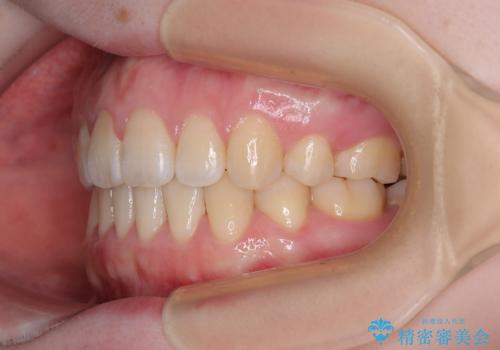

口元の突出感が改善されてことで、下唇に引っかかっていた上顎前歯も気にならなくなりました。